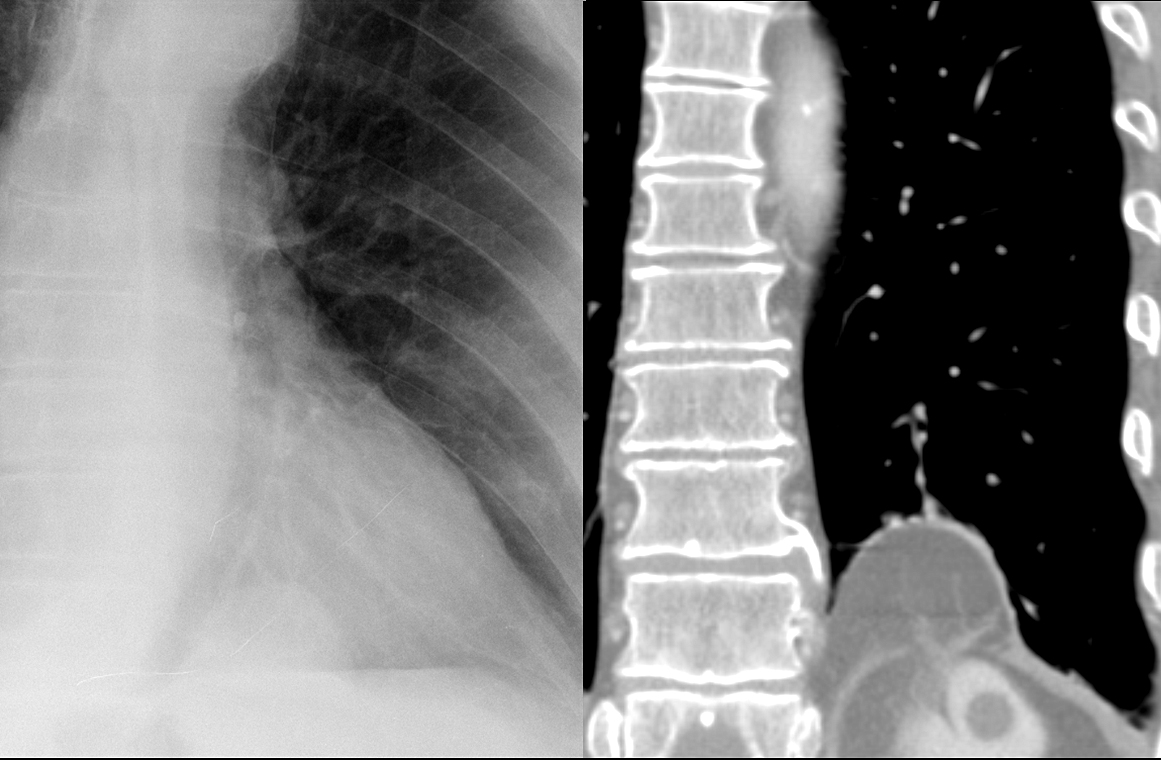

Gallery Congenital Bochdalek hernia PA

Bochdalek hernia PA